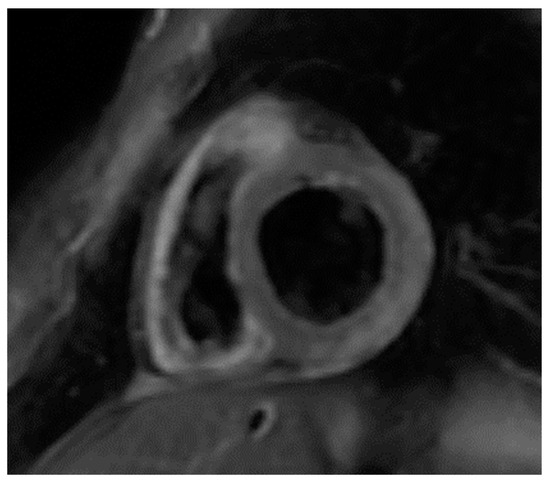

Currently, there is no specific algorithm for AIC using CMR. However, there is a diagnostic algorithm, by an expert consensus, using CMR for assessment of acute and chronic inflammatory cardiomyopathy [45]. According to this, in patients with suspected acute or active myocardial inflammation, apart from Lake Louise Criteria [44], the use of parametric mapping techniques (T2, native T1, post contrast T1, and ECV mapping) is recommended. While each parameter may indicate myocardial inflammation, the authors proposed that CMR provides strong evidence for myocardial inflammation, with increasing specificity, if the CMR scan demonstrates the combination of myocardial edema with other CMR markers of inflammatory myocardial injury (Figure 1 and Figure 2). This is based on at least one T2-based criterion (global or regional increase of myocardial T2 relaxation time or an increased signal intensity in T2-weighted CMR images), with at least one T1-based criterion (increased myocardial T1, extracellular volume, or late gadolinium enhancement).

Figure 1.

Short axis T2 image showing edema (bright area) in the lateral wall of LV of a patient with SLE presented with VT.